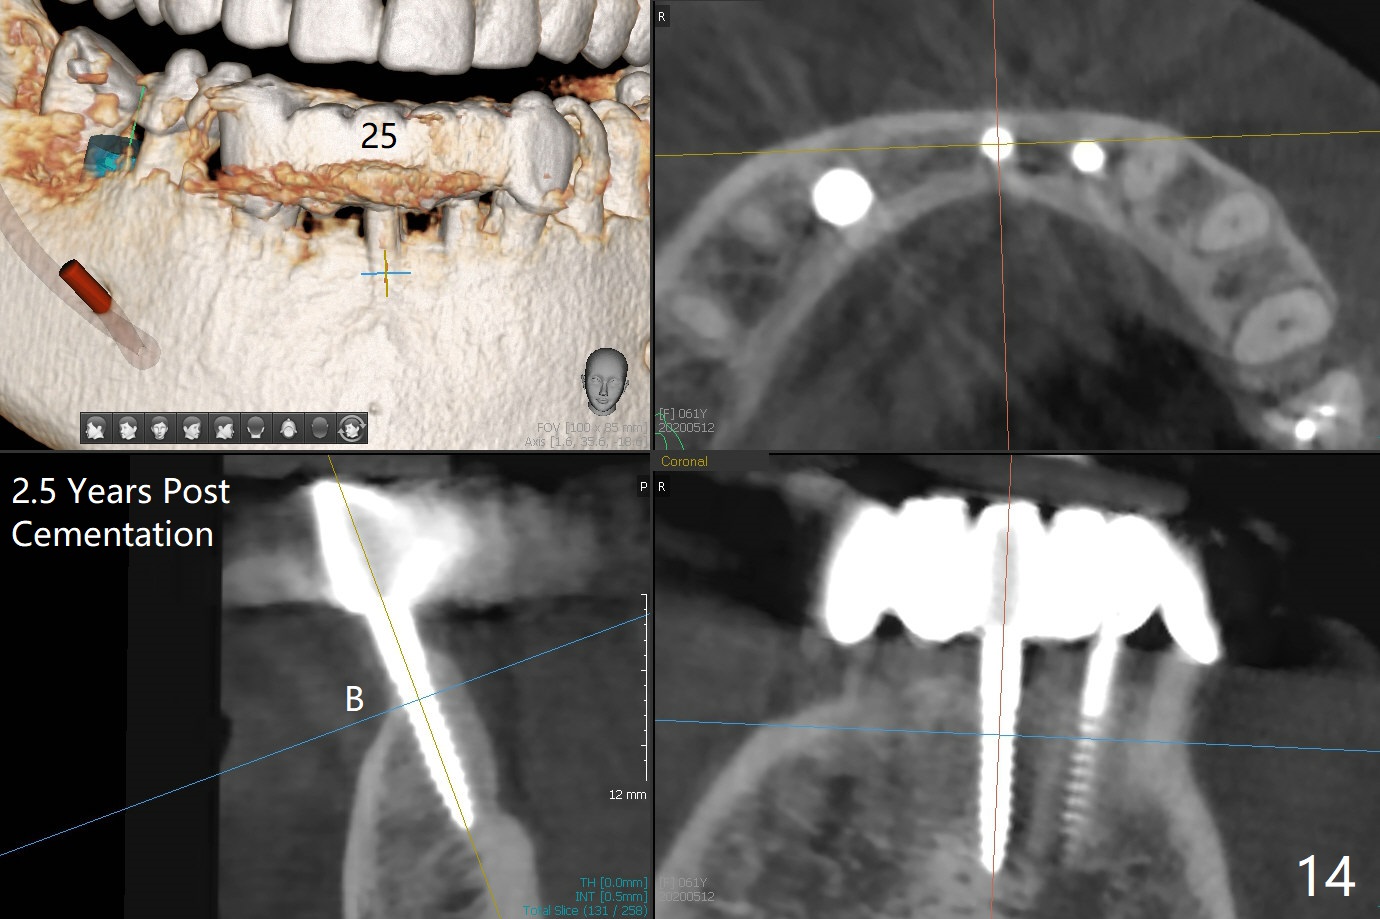

The mesial defect at #27 appears to have been repaired 8 months postop (Fig.8,9 *); there is no bone loss at 1-piece implant sites. The gingival recession seems to remain the same before and after removal of the provisional FPD (Fig.10,11). The bulging abutment at the cervix is less prominent when a straight abutment is used and prepared (Fig.12, 4.5x5.5(5) mm). There is no bone loss at #23, 25 and 27 sites 2.5 years post cementation (Fig.12-15), although the trajectory of the implants could be improved by using surgical guide (Fig.16-18).